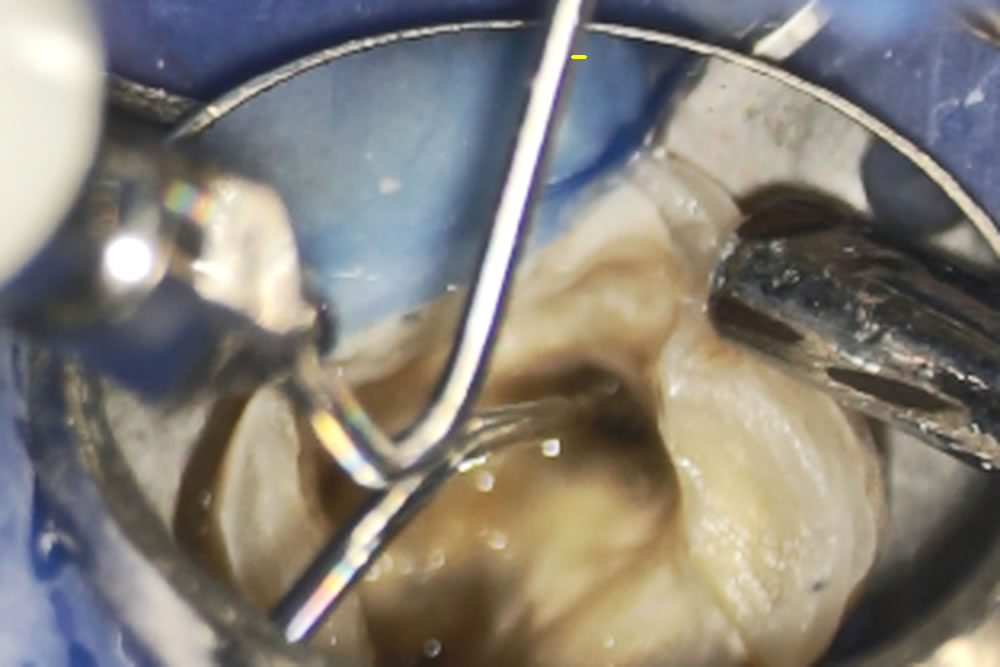

根管充填

根の中の消毒が終わったら、最終的な薬を詰めて根の中の空洞を封鎖する根管充填(こんかんじゅうてん)を実施。

MTAというセメントを根の中に詰めていきます。MTAセメントは殺菌したり、歯を再生させたり、穴の空いた歯の部分を埋めたりすることのできる新しい薬です。

MTAというセメントを根の中に詰めていきます。MTAセメントは殺菌したり、歯を再生させたり、穴の空いた歯の部分を埋めたりすることのできる新しい薬です。

通常、殺菌力の強い薬は歯や周りの組織に対しても悪い影響を与えますが、MTAセメントは体の組織に適度な刺激を与え、悪くなってしまった部分を再生させる作用があるお薬です。